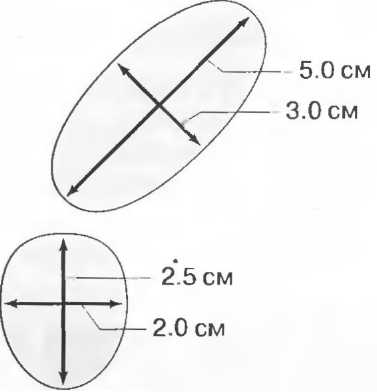

3. Ультразвуковые исследования в педиатрии. Для детей необходим датчик с частотой 5 МГц с глубиной фокусировки на 5-7 см. При исследовании мозга новорожденного используется секторный датчик с частотой 7,5 МГц с глубиной фокусировки на 4-5 см (этот датчик также используется для исследования яичек и структур шеи у взрослых).